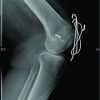

Case Report: We report the case of a 20-year-old female who presented 3 years after a conservatively treated distal radius fracture. Her complaints included wrist deformity, reduced grip strength, and intermittent pain. Imaging revealed a distal radius malunion with dorsal tilt and radial shortening, resulting in a positive ulnar variance of +4 mm, while the distal radioulnar joint (DRUJ) remained congruent. Surgical intervention involved an USO, during which a 1 cm wedge of bone was resected. At 1-year follow-up, she demonstrated excellent range of motion, full grip strength, no pain, and was highly satisfied with the cosmetic outcome.